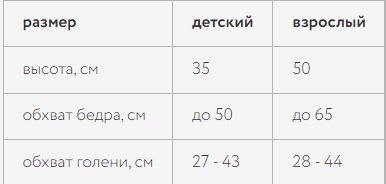

Подбор размера

Схема измерения

Таблица размеров

Подбор размера

Схема измерения

Таблица размеров